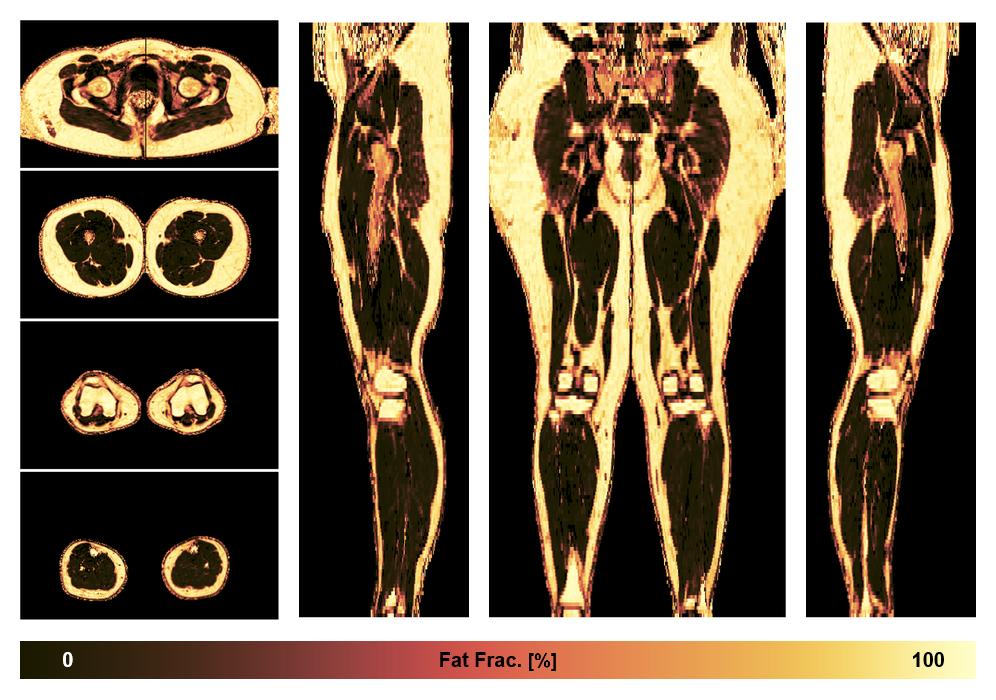

• Fat fraction

The fat fraction of the lower extremity obtained from the dixon reconstruction for muscle water fat quantification.